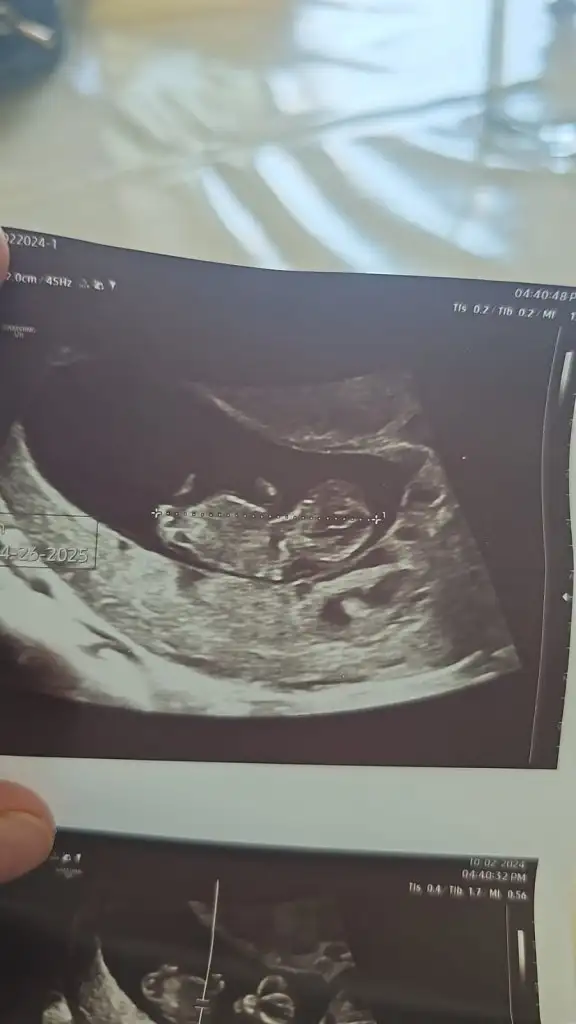

Kızlar selam. Yumurtlama sürecimi hiç takip etmediğim için maalesef bilmiyorum, bu konuda tecrübelerinize ve desteğinize ihtiyacım var. SAT 25 Şubat, 10 Mart'ta lekelenme ve ağrı başladı. Lekelenme ve ağrılar tam 16 gün sürdü, 25 Mart'ta bitti. Dayanılmayacak gibi değil fakat zaman zaman artan (ağrı kesiciye ihtiyaç duyulan), zaman zaman ise hafifleyen/kaybolan bel ve kasık ağrıları bu süre içinde hep devam etti. Reglden 14 gün sonra başladığı için yumurtlama olduğunu düşünüyorum. Ancak süre çok uzun geldi. Doktora gittim fakat net bir yorum yapamadı. Dış gebelik veya yumurtlama olduğunu düşünerek beta-hcg istedi. Pozitif çıkarsa tekrar gelirsin, negatif çıkarsa yumurtlamadır dedi. Sonuç negatif (2) çıktı, araya bayram da girince tekrar gidemedim. Henüz regl olmadım, reglimi hangi günden hesaplayacağımı da bilemiyorum. Sizce yumurtlayamama ya da yumurtamın çatlayamaması gibi bir durum olabilir mi? Veya dış gebelik, kimyasal gebelik tarzı bir şey? Benzer bir durum yaşayanınız oldu mu?

Ultrason görüntüsü de 17 Mart tarihine ait. Yani döngümün 21. günü. Belki USG ultrason görüntüsünden anlayan birileri çıkar :(